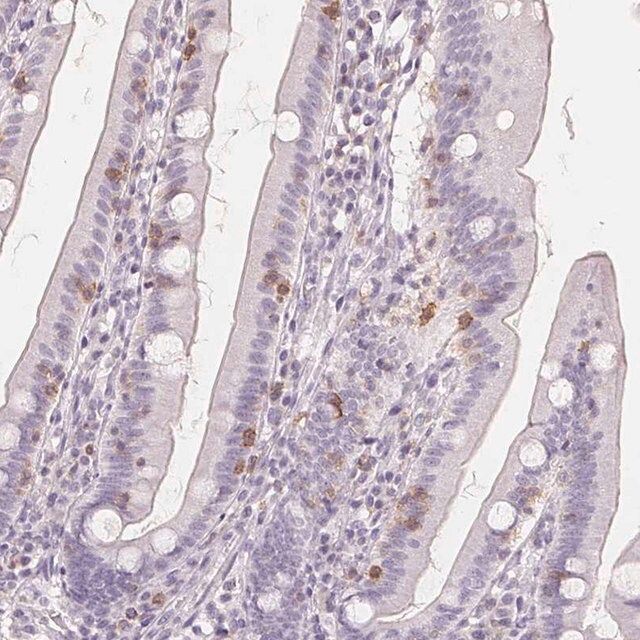

| General description【一般描述】 | Cluster of differentiation 69 (CD69) is a type II integral membrane protein, encoded by the gene mapped to human chromosome 12p13.31. CD69 is a member of the C-type lectin family of surface receptors. The encoded protein is expressed in all bone marrow-derived cells, with the exception of erythrocytes. |

| Biochem/physiol Actions【生化/生理作用】 | Cluster of differentiation 69 (CD69) exerts a pro-inflammatory effect by activating leukocytes. In humans, CD69 negatively regulates immune reactivity. Knockout/deficiency of the gene increases the risk of susceptibility to autoimmune and chronic inflammatory diseases. The encoded protein might act as a prognostic marker for bendamustine response in chronic lymphocytic leukemia (CLL) patients. CD69 facilitates natural killer (NK) cell function. In addition, it also helps in activation and differentiation of a wide variety of hematopoietic cells. |

| technique(s) | immunohistochemistry: 1:50- 1:200 |